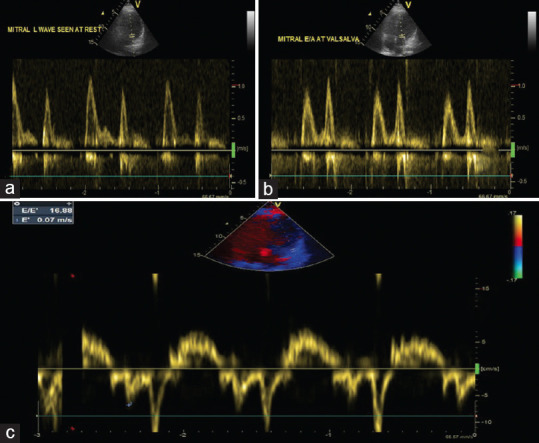

二尖瓣 L 波:晚期舒张功能障碍的标志。

The Mitral L-wave: A Marker of Advanced Diastolic Dysfunction.